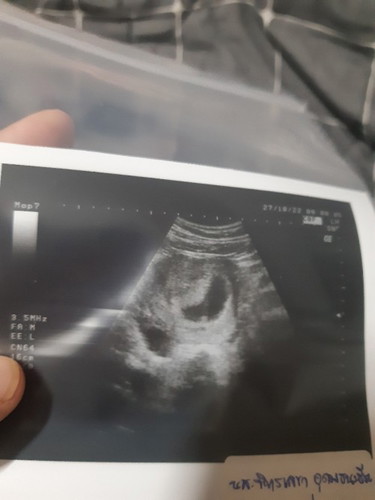

ไปซาวด์มาแล้ว ขนาดตัวน้องเล็กมากแทบมองไม่เห็นเลยค่ะ หมอบอกไม่สามารถบอกอายุครรภ์ได้เพราะปจด.มาไม่ปกติ

ในแอพบอก8W #ท้องแรกคะ

ในแอฟเขาจะคำนวณให้ค่ะถ้าเราใส่วันที่เป็นปจด.ครั้งล่าสุด คุณหมอก็ดูจากปจด.ล่าสุดเหมือนกัน ถ้า8wคือต้องเห็นน้องแล้วนะคะ ได้ยินเสียงหัวใจด้วย